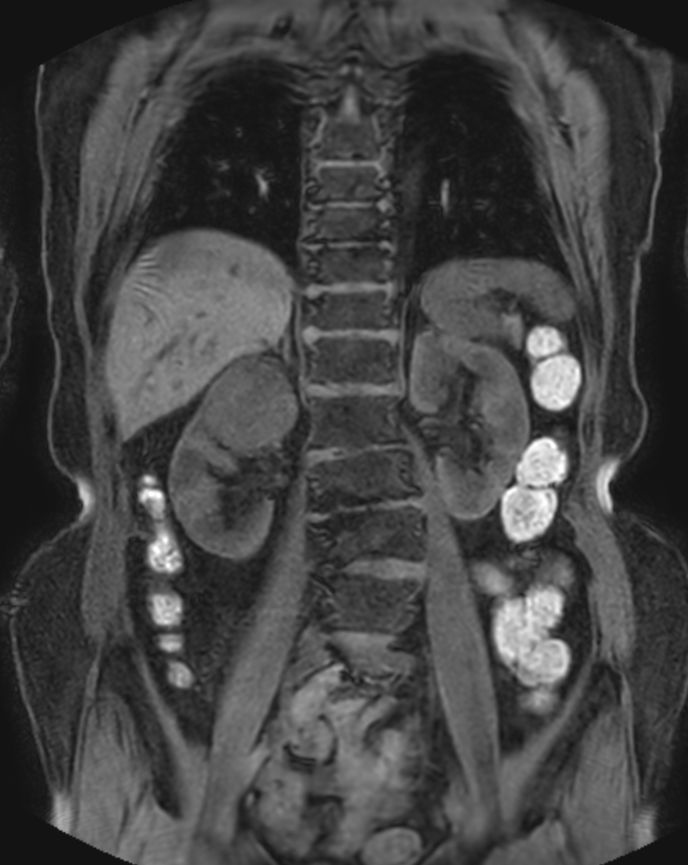

Patient with renal failure. ExamCard includes MultiVane XD to acquire motion-free diagnostic images and 4D FreeBreathing to perform multi-phase contrast-enhanced MRI studies.

T2w SPIR MultiVane XD - Free Breathing